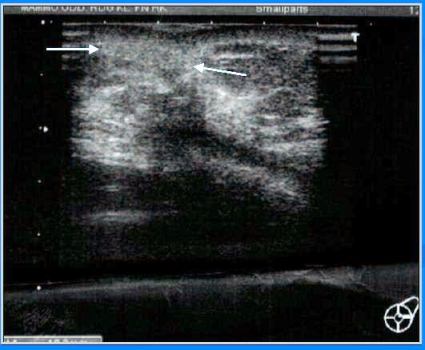

- MMG – ohraničená léze 40x45mm

- UZ – heterogenní, izo a hypoechogenní, ostře ohraničené ložisko

- Dg. – intracyst.tumor?

- HI: Epidermoidní cysta

- MMG – ohraničené laločnaté ložisko sin

- UZ – ohraničená anechogen.léze se solidní izoechogen.porcí

- Dg. – intracystický tumor?

- CCB HI: invazivní duktální Ca